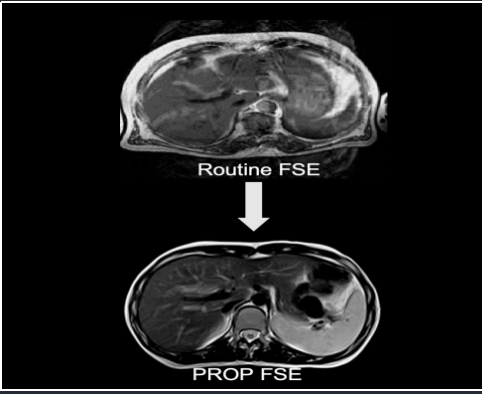

Công nghệ điền dữ liệu PROP

Giảm nhiễu do chuyển động mà không làm mất thông tin hình ảnh, áp dụng đối với bệnh nhân khó giữ yên